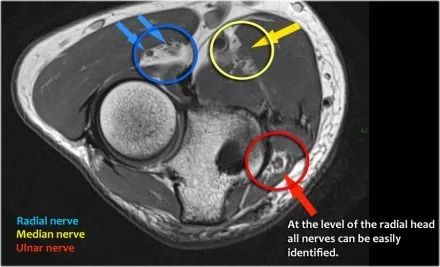

桡神经:在桡骨头水平可以最好地识别桡神经,在那里你可以看到桡骨隧道中的浅表和深支(箭头)。这是寻找桡神经的非常一致的地方。